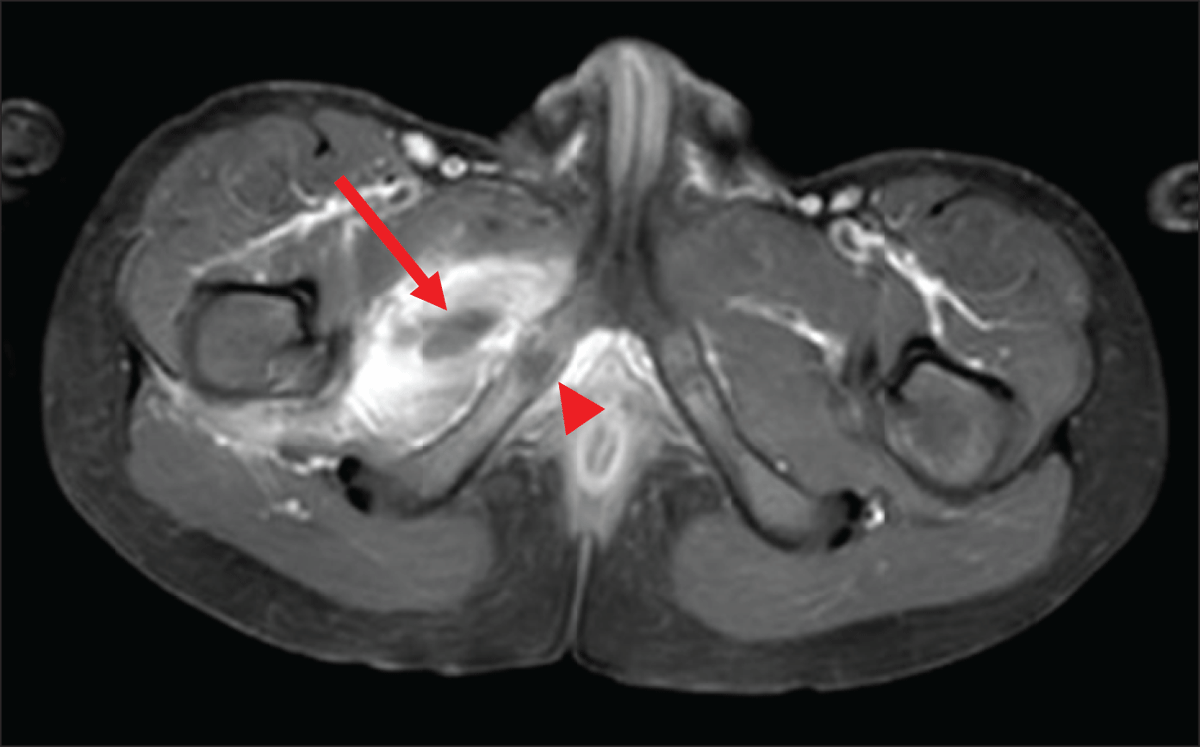

At this time, the blood analysis showed high white blood cells (18.500/mm3) and CRP (171.6 mg/L). Magnetic resonance imaging (MRI) (Figures 1, 2, 3) revealed a 3 cm long subperiosteal collection in contact with the right ischiopubic synchondrosis (arrowheads), suggestive of an abscess (arrows on axial. Figure 1, and coronal, Figure 2, post-contrast fat-saturated T1-weighted images). The abscess extended to the proximal part of adductors compartment and the right ischiopubic branch was involved by edema, appearing as high signal on short-tau inversion-recovery (STIR) imaging (Figure 3). Extensive edema was also visible in the surrounding tissues.

Figure 1